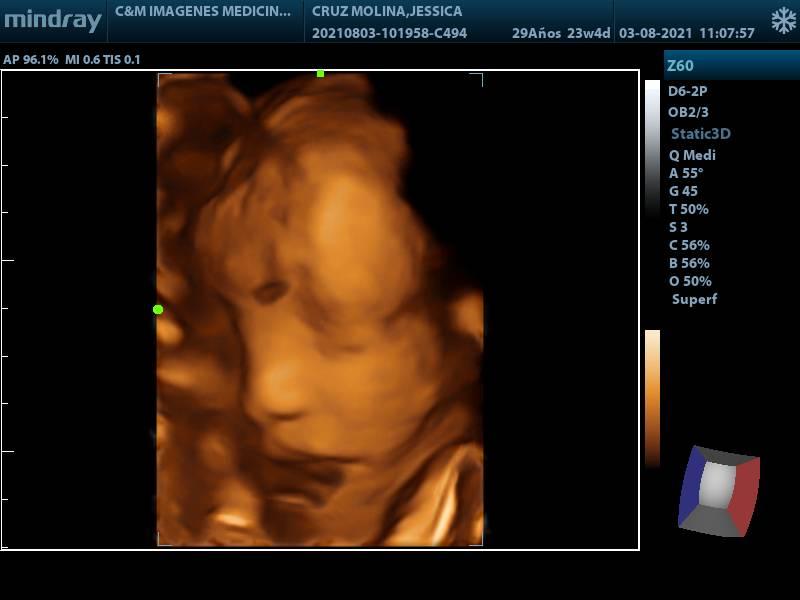

ECOGRAFIA OBSTETRICA 3D

SERVICIOECOGRAFIA

CONDICIÓNCUALQUIER EDAD GESTACIONAL

ESPECIFICACIONESIMAGEN TRIMIDENCIONAL DEL FETO SE ESTUDIA BIOMETRIA FETAL ILA VALORACION PLACENTA LATIDOS CARDIACOS FETALES